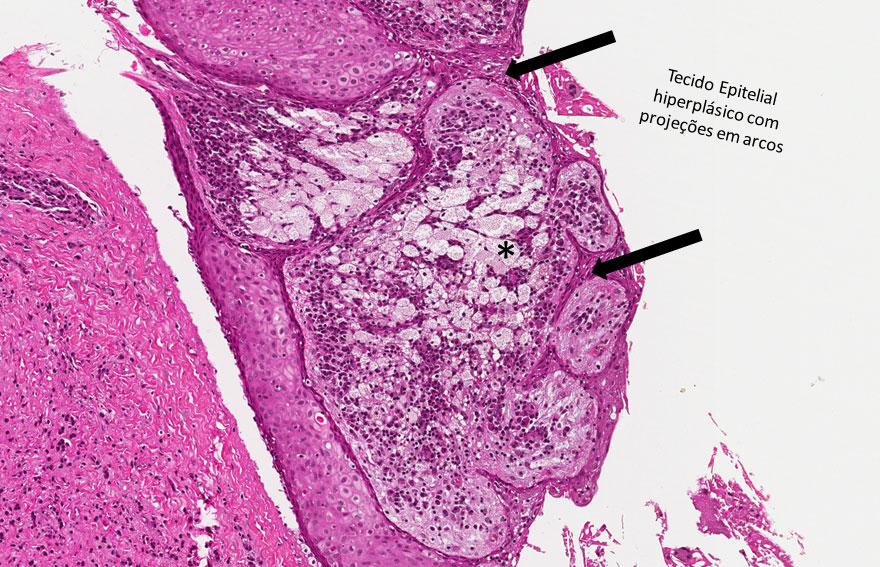

Cavidade revestida por tecido epitelial estratificado pavimentoso não ceratinizado. No centro observa-se o lúmen cístico com restos celulares no interior. Circundando o revestimento epitelial observa-se infiltrado inflamatório linfoplasmocitário, cápsula fibrosa (Figura 7) e cristais de colesterol (Figura 11).

Observar a cavidade cística, o tecido epitelial revestindo esta cavidade (Figuras 8 e 9). O epitélio em áreas está hiperplasiado e fazendo projeções em arcos para o interior do tecido conjuntivo (Figuras 8 e 9). A cápsula fibrosa está envolvendo o epitélio e no seu interior observam-se células inflamatórias principalmente plasmócitos (asterisco amarelo — Figura 10) e linfócitos (asterisco verde — Figura 10). Em área focal pode-se evidenciar macrófagos espumosos (asterisco preto — Figura 8).

Cisto Apical